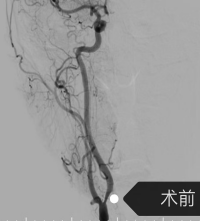

近日,我院神经内科脑血管介入团队,再次成功为一名女性患者实施了“经桡动脉入路脑血管造影+颈内动脉支架植入术”。该患者曾因脑梗死住院期间检查发现右侧颈内动脉存在重度狭窄,狭窄率达80 %。如同给大脑供血的“主干道”出现了严重拥堵,随时可能因血流中断导致致命性脑卒中。

手术当日,神经内科介入团队娴熟操作介入设备,导丝、导管、支架系统操作顺利送达指定部位,成功将支架输送至狭窄部位并精准释放,瞬间打通了狭窄严重的血管,恢复了大脑的正常供血,整台手术流畅顺利,采用局部麻醉,患者全程清醒,无身体不适反应。